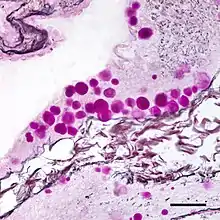

Corpora amylacea (CA) (from the Latin meaning "starch-like bodies;" also known as wasteosomes[1]) is a general term for small hyaline masses found in the prostate gland,[2] nervous system,[3] lung,[2] and sometimes in other organs of the body.[4] Corpora amylacea increase in number and size with advancing age,[4][5] although this increase varies from person to person.[4] In the nervous system, they are particularly abundant in certain neurodegenerative diseases.[3] While their significance is largely unknown, some researchers have suggested that corpora amylacea play a role in the clearance of debris.[2][4]

The composition and appearance of corpora amylacea can differ in different organs.[4] In the prostate gland, where they are also known as prostatic concretions, corpora amylacea are rich in aggregated protein that has many of the features of amyloid, whereas those in the central nervous system are generally smaller and do not contain amyloid.[4] Corpora amylacea in the central nervous system occur in the foot processes of astrocytes, and they are usually present beneath the pia mater, in the tissues surrounding the ventricles, and around blood vessels.[3] They have been proposed to be part of a family of polyglucosan diseases, in which polymers of glucose collect to form abnormal structures known as polyglucosan bodies.[4] Polyglucosan bodies bearing at least partial resemblance to human corpora amylacea have been observed in various nonhuman species.[4]